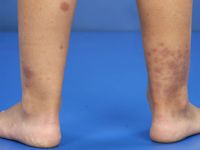

HENOCH SCHÖNLEIN PURPURA / IgA VASCULITIS home ICD10: D69.0

Henoch-Schönlein purpura (Henoch-Schönlein vasculitis, IgA vasculitis) is een IgA-gemedieerde vasculitis met petechiën en/of palpabele purpura en vaak een systemische component, vooral nierschade (IgA nefropathie; frequent ook IgG gericht tegen mesangiale cellen), voorbijgaande arthralgiën (knie, enkel), en buikklachten (buikpijn, bloedingen, zelden intussusceptie, pancreatitis, cholecystitis, protein-losing enteropathy). Soms ook in andere organen (longen, CZS). Het komt vooral voor bij kinderen (de helft is onder de 5) en jong-volwassenen, en wordt vaak voorafgegaan door een luchtweginfectie. In Nederland is de incidentie 6.1 per 100.000 kinderen. HSP kan optreden na infecties met streptokokken (Groep A, ß-hemolytisch), hepatitis B, herpes simplexvirus, parvovirus B19, Coxsackievirus, en adenovirus. De diagnose kan bevestigd worden met een biopt, een HE-biopt en een IF biopt, maar het is niet altijd nodig om een biopt te nemen, de diagnose kan ook gesteld worden op het klinisch beeld.

De term Henoch Schönlein purpura of vasculitis wordt gebruikt voor het klassieke patroon van purpura, nierschade, arthralgiën en buikklachten bij kinderen, de andere (overkoepelende) term die gebruikt wordt is IgA-vasculitis.